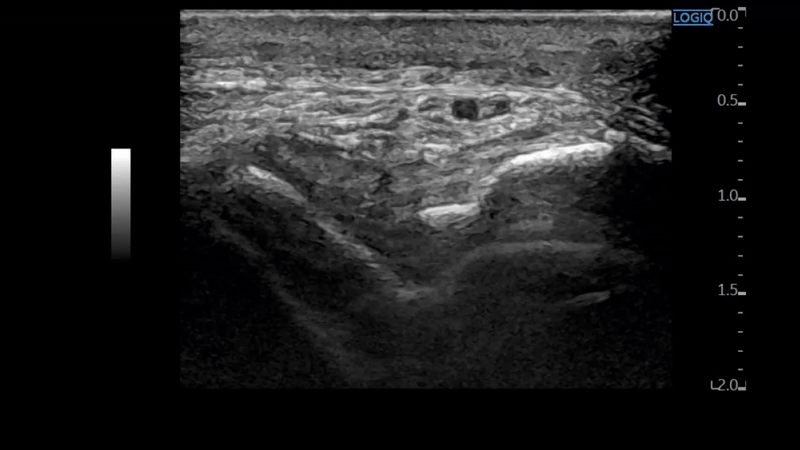

족소양경근에 프로브를 대어

반대쪽과 비교해보았습니다.

왼쪽 영상을 보시면

이분인대가 늘어나면서

종골 전방돌기(anterior process)가

톡 떨어져 나갔네요.

주변 연부 조직도 부어있어

골절이 의심됩니다.